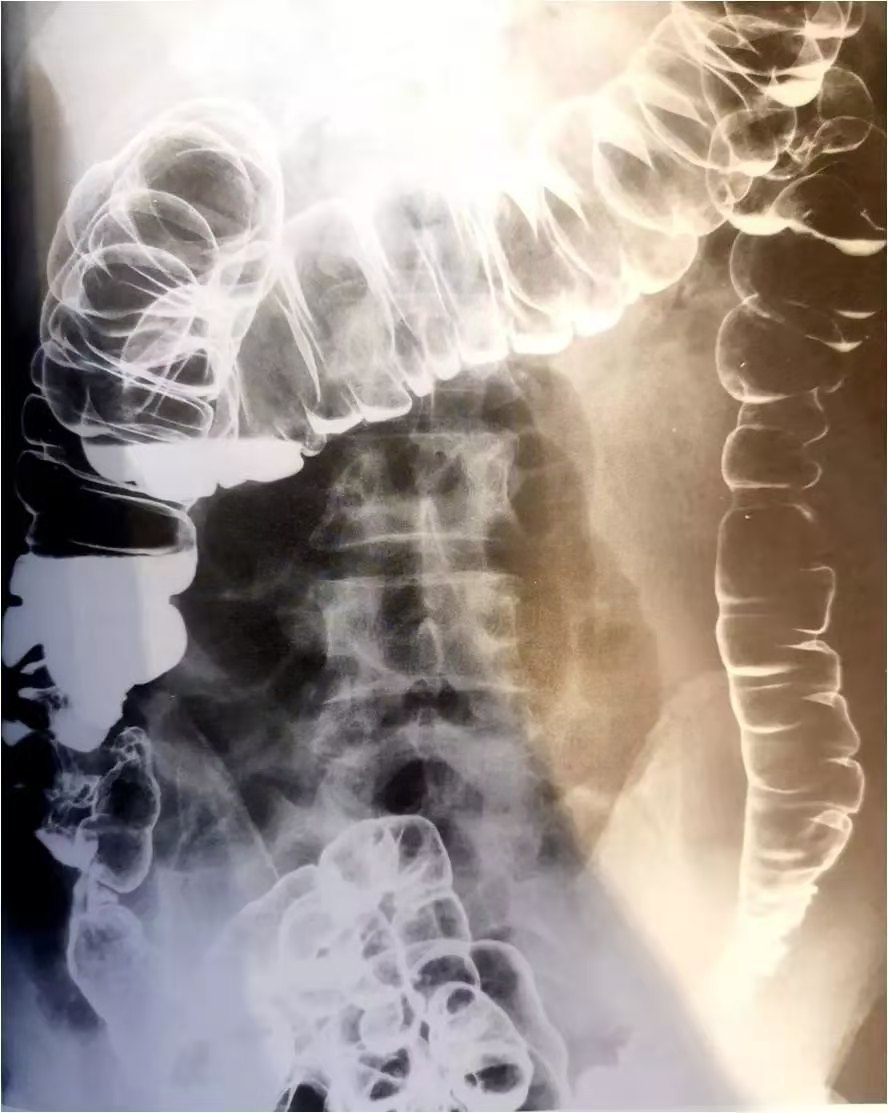

2、X线钡餐检查

在检查是否患有溃疡性结肠炎时,也同样可以选择这种方法,但是这种方法并不适合在急性期使用,一般在重度溃疡结肠腺炎出现时,如果使用灌肠检查就有可能会造成并发症,比如可能会诱发大肠穿孔的可能性。而对于一般的病人来说,在选择这种检查方法之后,也会发现有明显的圆形充盈缺损,这也是判断疾病的一种方法。